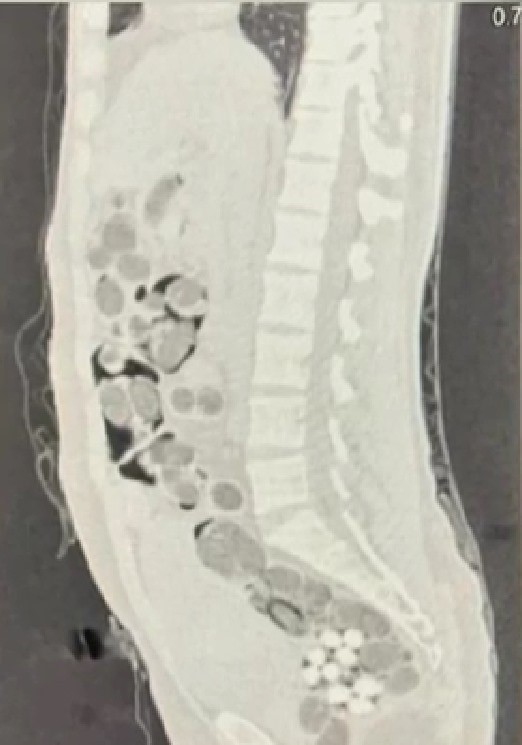

Yapılan takibin sonucunda şüphelinin yurt dışından getirdiği uyuşturucu maddeleri teslim edeceği kişiyle buluştuğu sırada operasyon düzenlendi. Operasyon sonucunda iki yabancı uyruklu şüpheli gözaltına alındı. Uyuşturucu madde kuryesi olan şüpheli şahsın üzerinde yapılan iç beden muayenesinde doğal yollarla yutmuş 177 paket halinde toplamda 1 kilo 144 gram skunk maddesi, 38 paket halinde 178 gram metamfetamin maddesi, 3 paket halinde 90 adet uyuşturucu hap, 1 paket halinde 7 gram Afyon sakızı maddesi olmak üzere toplam 219 paket uyuşturucu ve uyarıcı madde ele geçirildi.

Midesinde 219 paket uyuşturucu madde taşıdığı tespit edilen uyuşturucu kuryesinin hastanede müşahede altına alındığı, hastanede 5 gün müşahede altında kaldığı süre boyunca 219 paket uyuşturucu maddenin doğal yollarla midesinden çıkartıldığı ifade edildi. Hastanede işlemlerinin ardından uyuşturucu veya uyarıcı madde ticareti yapmak suçundan adli makamlara sevk edilen yabancı uyruklu kurye ve yine yabancı olan zehir taciri tutuklanarak cezaevine gönderildi.